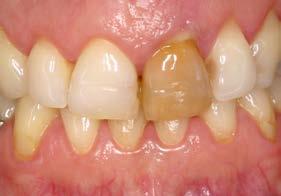

Figuras 1 y 2. Imágenes iniciales de la paciente. Se observa el diente en posición 21 con un cambio de color evidente y supuración espontánea a través del surco gingival. Asimismo, se aprecia el impacto estético del cambio cromático en la sonrisa y en el aspecto del frente anterosuperior.

Caso clínico

Se presenta el caso de una paciente femenina de 47 años de edad al inicio del tratamiento, quien acude a consulta por dolor y supuración en el incisivo central superior izquierdo. En las imágenes iniciales se observa un diente con un cambio de color llamativo y una supuración espontánea a través del surco gingival (Figura 1). Esta alteración cromática, además de reflejar un problema asociado al diente, afecta de manera significativa la estética del frente anterior, como se aprecia en la imagen de sonrisa (Figura 2).

El diente había sufrido un traumatismo durante la infancia de la paciente y, tras la pérdida de vitalidad pulpar,

Estos hallazgos confirman el éxito del procedimiento quirúrgico y de la posterior carga progresiva, con un mantenimiento óptimo de los tejidos duros y blandos a lo largo de más de dos décadas (Figura 15). Los cambios entre el momento inicial y el final del tratamiento son evidentes, especialmente al comparar la imagen intraoral de la primera visita con la tomada a los 22 años, donde la mucosa que rodea al diente 21 —y posteriormente al implante— se muestra engrosada, en buen estado de salud y con una estética destacable. Asimismo, la comparación entre la radiografía inicial, que evidenciaba el fracaso del tratamiento de conductos del diente en posición 21, y la radiografía a los 22 años, que muestra el implante sin pérdidas óseas asociadas, resulta elocuente (Figuras 16 a 19).

Figuras 16 y 17. Comparación entre la imagen inicial —diente con cambio de coloración, encía inflamada y pérdida de grosor— y la obtenida a los 22 años, que muestra estabilidad y salud gingival con el implante.